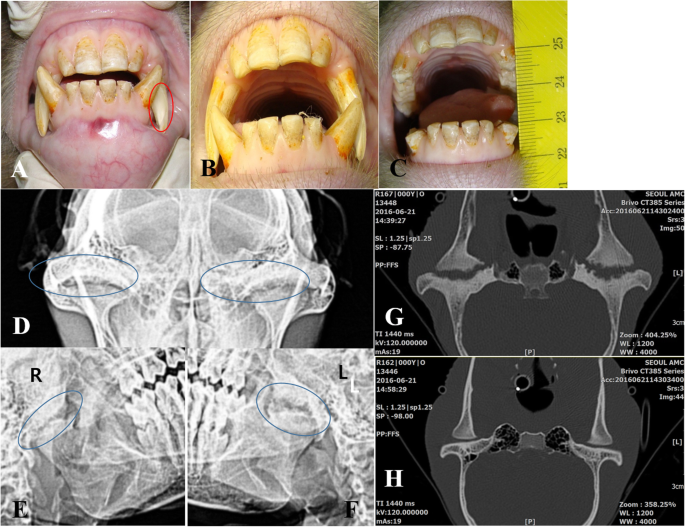

TMJs coronal axial and sagittal views teeth clenched on mandibular appliance made by the dentist condylar position altered just enough to allow a reduction in compression posteriorly medially and slightly superiorly in the joint. If playback doesnt. Degenerative joint disease DJD a common osteoarthritic problem encountered in clinical practice presents as a chronic debilitating disease resulting in altered joint structure due to degradation and loss of articular cartilage along with changes in.

Spectrum Of Temporomandibular Joint Remodeling Following Orthognathic Download Scientific Diagram